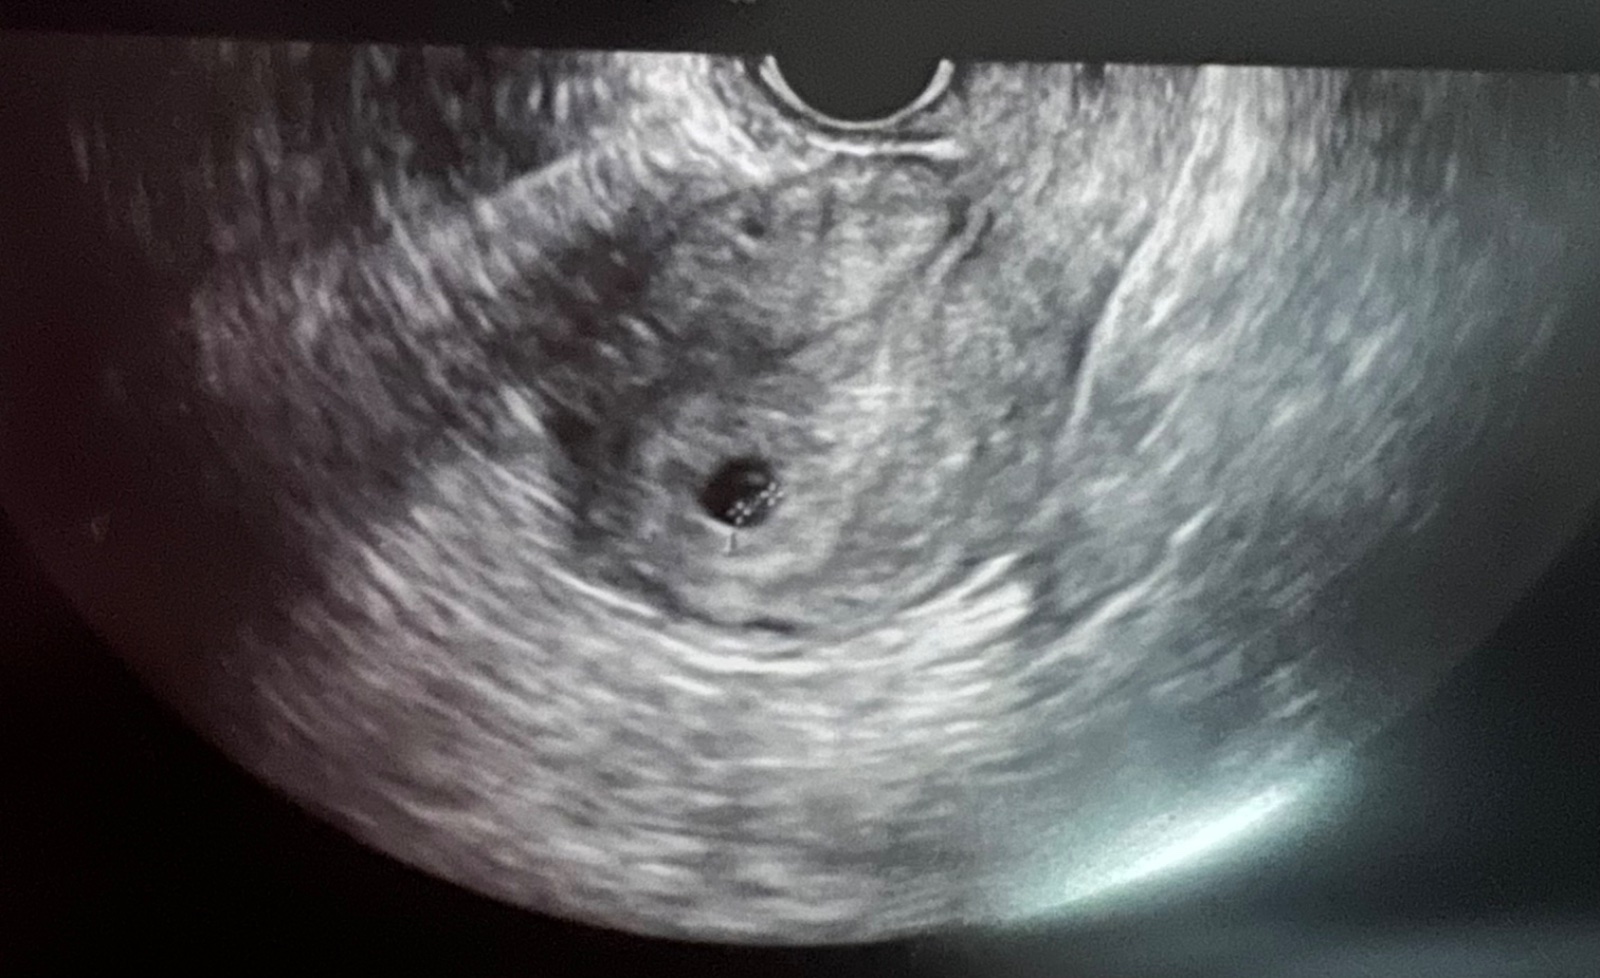

7.1. Videl doktor toto

@anonym_afd62e mas to ako ja. A o týždeň si bola na kontrolu a ako bolo vidieť ?

@olivia20 videl už aj zltkovy vak a zárodok plodu zatiaľ bez akcie srdca